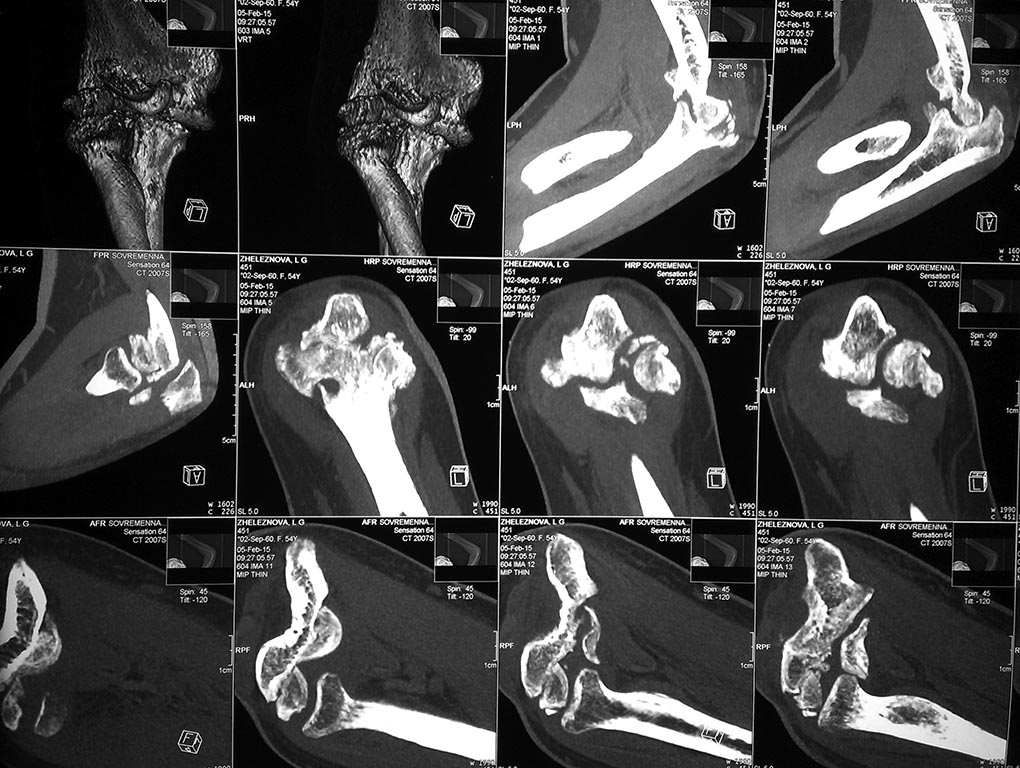

У женщины 54 лет имеются последствия закрытого вывиха костей предплечья...

Травма 08.11.14 г., окончательное вправление лишь 10.11.14 г., тогда же

появились признаки нейропатии локтевого нерва, они остаются до сих пор.

Движения в суставе качательные, практически анкилоз в положении 90 град.

Снимки КТ в приложении. Уважаемые травматологи-ортопеды! Что делать в

такой ситуации? Эндопротез? Релиз? Ничего?